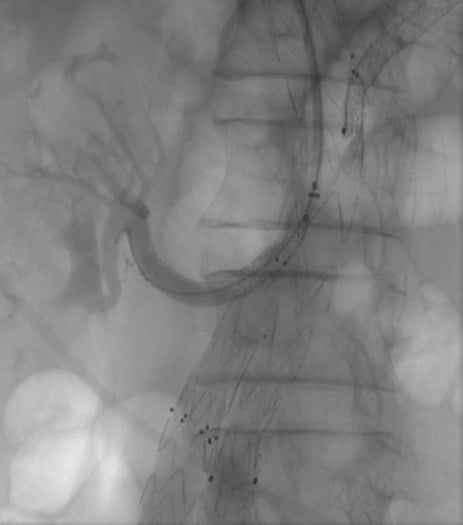

- After pneumoperitoneum induction, the flaccid part was opened and splenic, left gastric and hepatic arteries were identified and carefully isolated.

- The vessels were temporary clamped and green indocyanin was injected to exclude visceral ischemia.

- So, finally, the celiac trunk was closed with a clip at its origin from the aorta.

Robotic celiac trunk ligature

- Type II endoleak (A);

- Celiac branches temporary robotic clamping (B);

- Check with indocyanin green injection (C);

- Type II endoleak complete resolution after celiac trunk ligature (D).